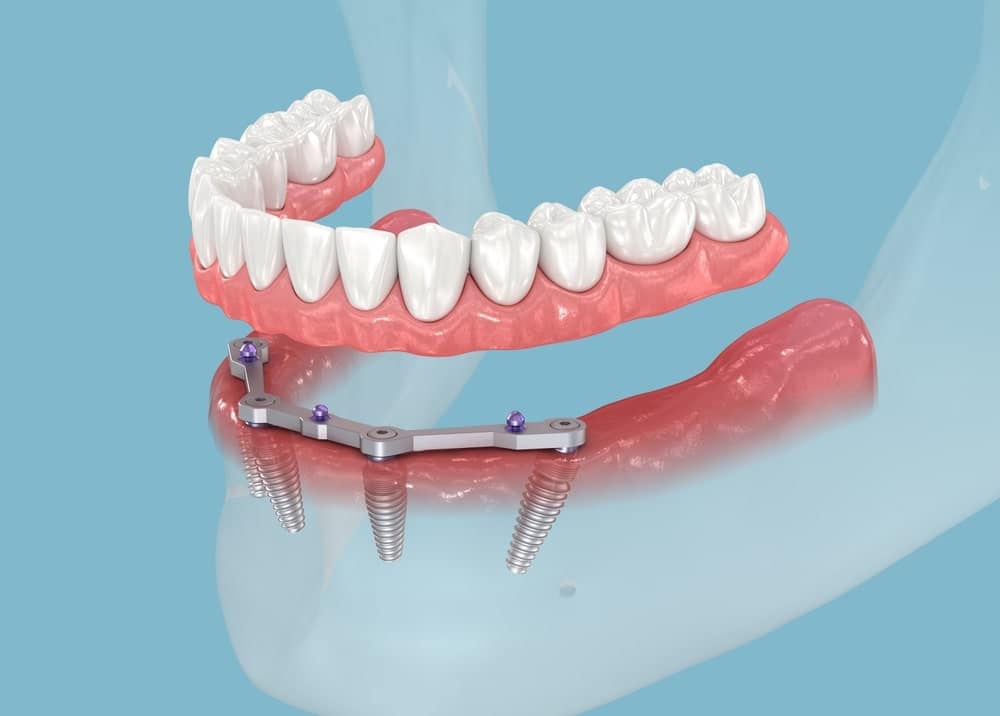

La prothèse sur implants : quels sont les avantages ?

Les prothèses sur implants offrent une solution moderne et efficace pour remplacer des dents manquantes. Si vous cherchez une option qui combine confort, fonctionnalité et esthétisme, cela pourrait être idéale pour vous. Voici un aperçu des principaux avantages de la prothèse sur implants, ainsi que des informations sur la manière dont l’équipe du Centre Dentaire Taschereau peut vous...